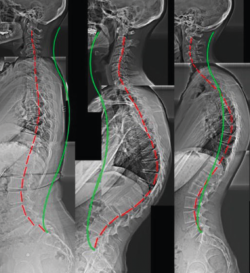

Figura 5. Espondiloartropatía degenerativa.

Otros hallazgos radiológicos frecuentes, como las anomalías congénitas de transición lumbosacra, espondilolistesis, secuelas de epifisitis, la espina bífida oculta, las escoliosis leves o moderadas, la hiperlordosis, espondiloartropatía, etc., se encuentran casi por igual en pacientes con y sin dolor lumbar (Figuras 5, 6 y 7)(22,23).

Figura 6. Secuelas de epifisitis. Reproducido de Perolat et al.(22).

Figura 7. Hiperlordosis. Reproducido de Oakley et al.(23).